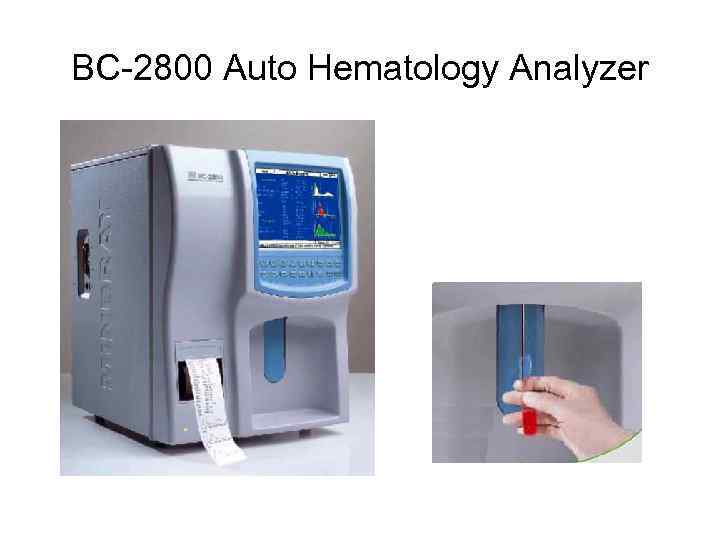

BC-2800 Auto Hematology Analyzer

BC-2800 Auto Hematology Analyzer